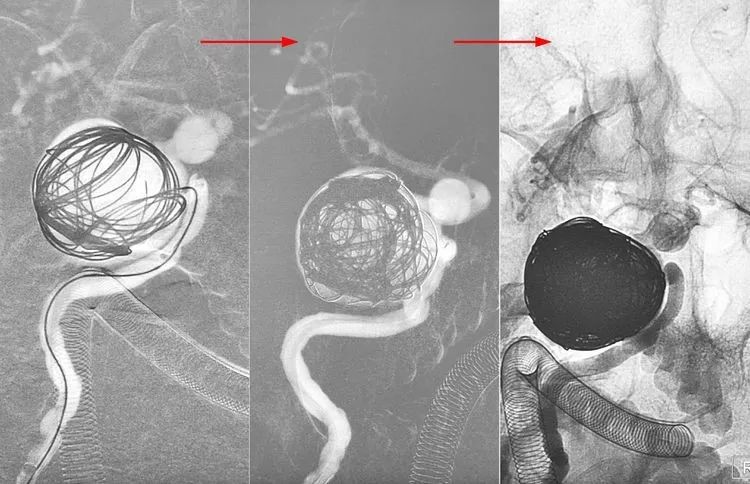

1个半月后二期行密网支架置入。

5F Navien中间导管置入右颈内动脉岩骨段,行右颈内动脉造影显示大瘤大部栓塞,瘤颈处开放。

Echelon-10微导管(头端塑成猪尾形)在Synchro-14微导丝(200cm)引导下顺利越过两个动脉瘤进入远端的大脑中动脉内。

应用Synchro-14微导丝(300cm)交换技术,撤离Echelon-10微导管,交换入T-track支架导管,经支架导管输送Tubridge®密网支架(4.5×45mm),支架头端锚定于右侧大脑中动脉起始部。

完全释放Tubridge®密网支架。

术后右颈内动脉正侧位造影显示:右大脑前动脉不显影,考虑为血流动力学因素所致。